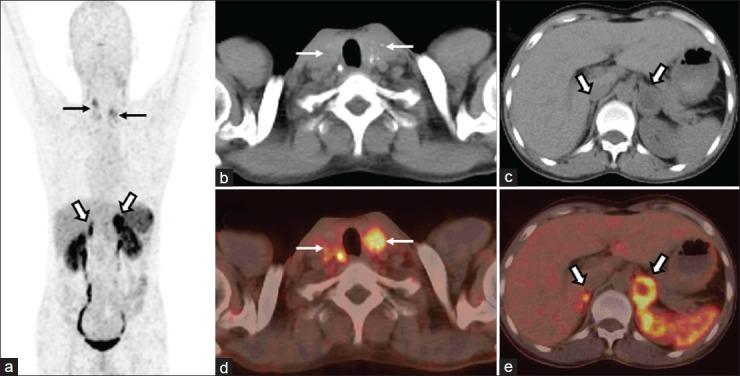

Neuroendocrine tumors (NETs) are rare neoplasms characterized by overexpression of somatostatin receptors (SSTRs). Functional imaging plays a crucial role in management of NETs. Recently, positron emission tomography/computed tomography (PET/CT) with (68)Gallium ((68)Ga)-labeled somatostatin analogues has shown excellent results for imaging of NETs and better results than conventional SSTR scintigraphy. In this review we have discussed the utility of (68)Ga-labeled somatostatin analogue PET/CT in NETs for various established and potential indications. In addition we have also shared our own experience from a tertiary care center in India.

神经内分泌肿瘤(NETs)是一种罕见的肿瘤,其特征是生长抑素受体(SSTRs)过度表达。功能成像在NETs的管理中起着至关重要的作用。最近,使用(68)镓((68)Ga)标记的生长抑素类似物的正电子发射断层扫描/计算机断层扫描(PET/CT)在NETs成像中显示出优异的结果,并且比传统的SSTR闪烁扫描结果更好。在这篇综述中,我们讨论了(68)Ga标记的生长抑素类似物PET/CT在NETs中用于各种既定和潜在适应症的效用。此外,我们还分享了我们在印度一家三级医疗中心的经验。